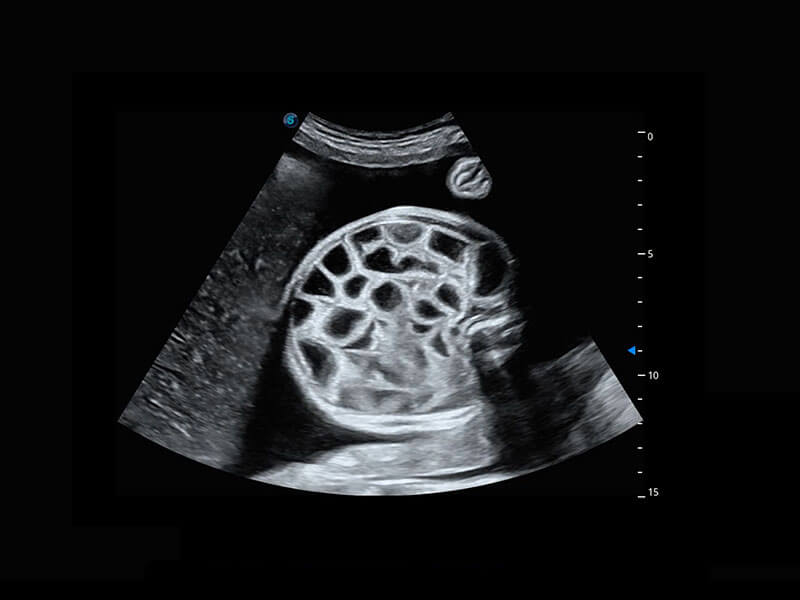

生殖健康

P60优异的图像质量搭载专科探头,在妇科基础疾病的诊断、卵泡生长的监测、输卵管通畅情况的判别等方面为您提供生殖应用方案。

• 腔内妇科-宫腔分离

• 腔内妇科-卵巢